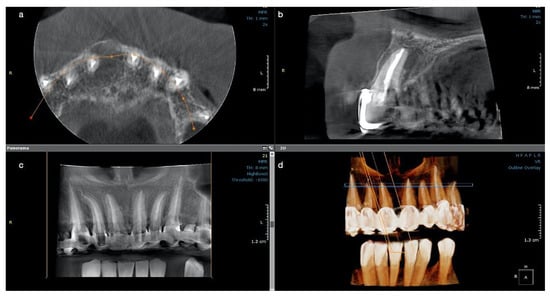

Pulp vitality testing using cold ice showed a negative response only for tooth #11 and a normal response for tooth #12. A negative response was also obtained for tooth #11 for both warm and electric pulp testing. Both teeth presented no tenderness in the long axis percussion test. Periodontal probing was within normal limits for both incisors and the gingiva was intact. The patient had already been subjected to a CBCT investigation with the parameters 11 × 5 cm field of view, 150 µm voxel size, 90 kV, 14 mA, and 5.07 s emission, being a referral case, so the CBCT was analyzed for a precise diagnostic by the endodontist. The images were displayed on a 24” Dell Flat Panel Monitor (Dell, Bucharest, Romania) with 1920 × 1080 pixels resolution. A large unilocular radiolucent lesion, which involved the periapical region of tooth #11, extending distally up to the lateral incisor, without involving its apex, mesially to the middle line of the maxilla, and up to the nasal fossa, with an intact nasal floor, was diagnosed. The size of the lesion was measured using the measurement tools of the Planmeca Romexis software (Planmeca, Helsinki, Finland), and it was about 9 mm in height, 9 mm in the buccolingual direction, and 10 mm in the mesiodistal direction. The lesion appeared well outlined, with a thin radiopaque border on all its contours, but communicated with the apex of the central incisor in its inferior part (Figure 1a–c).

Post-operative instructions were given to the patient, and she was kept under observation. At the 2-week check-up, a significant reduction in size of the swelling was observed, with no symptomatology of the patient, and after a further month, the swelling had completely disappeared; an increased resistance at palpation in the buccal apical region of the tooth #11 was noticed. After three months, a palpable portion of the buccal bone in the central incisor’s region was observed. At the 6-months follow up, only a control periapical radiograph was taken and a major decrease of the cyst-like lesion, with almost complete healing and formation of new trabecular bone, were observed (Figure 1d).

The patient was recalled at 12 months, and another CBCT with parameters 5 × 5 cm field of view, 85 µm voxel size, 90 kV, 6.3 mA, and 8.70 s emission was performed in the dental clinic to observe the evolution of the lesion. The OnDemand3D (OP 3D™ Pro, KaVo Dental GmbH, Biberach, Germany) program was used for analysis and new measurements on the same computer screen. In all three sections, the lesion appeared almost completely healed; the buccal and alveolar bone were completely restored and the contour of the periodontal ligament was normal, with a small area of enlargement, of only 1.5 mm, around the apex of the tooth (Figure 1e–h). Tooth #12 was still vital, with a normal response. At present, the patient has no symptomatology, the tooth is functional, and the 18-month control will follow.

Figure 1. Case 1. Radiological investigations for tooth #11: (ac) Initial CBCT scans with the measurements of the lesion’s size, indicated by blue arrows: mesiodistal diameter 9.75 mm, height 9.31 mm, buccolingual diameter 10.36 mm, with the interruption of the cortical buccal plate (9.75 × 9.31 × 10.36 mm); (d) control periapical X-ray at 6 months, showing the quality of the endodontic treatment and almost the complete healing of the lesion; (eg) CBCT scans at 12 months showing the intact buccal cortical plate, the formation of new bone, and the almost complete healing of the lesion. A small enlargement of the periodontal ligament space is still observed apically, (h) 3D reconstruction where intact maxillary bone is observed.